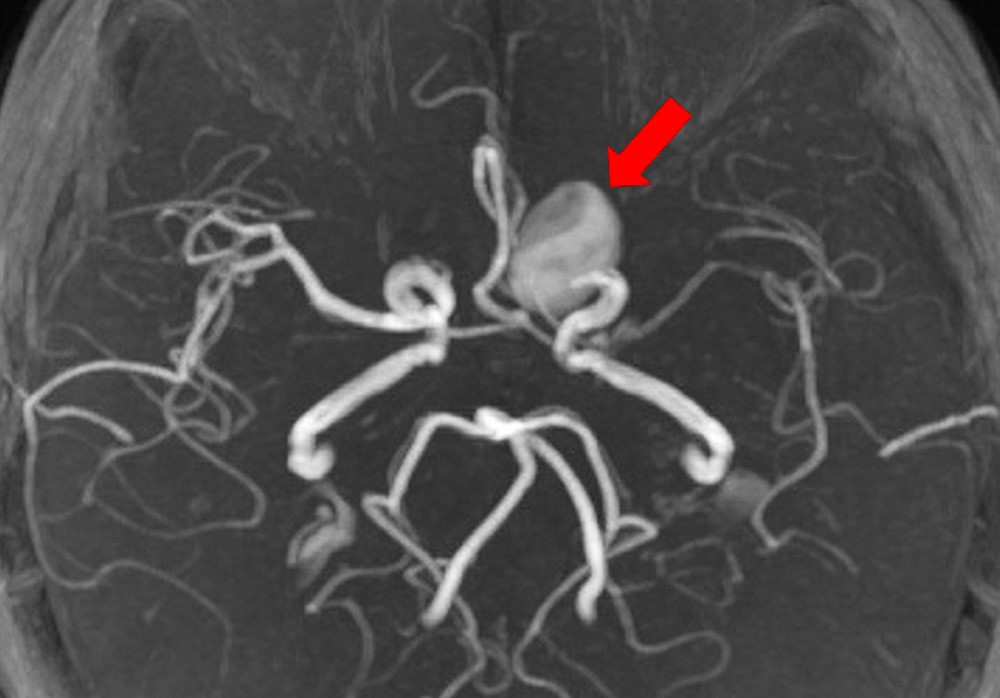

艾小姐平時作息正常,無不良嗜好,長期感到頭暈、胸悶不適,有天突發性昏厥,被送來台北慈濟醫院急診室,急診醫師評估後立即安排腦部的電腦斷層檢查,發現疑似腦部腫瘤,遂進行磁振造影,確定艾小姐的顱內有一個約兩公分的巨大動脈瘤,比一般常見約零點三到零點五公分的動脈瘤大了許多。於是由影像醫學部神經血管介入治療科阮郁修醫師評估及治療。阮醫師運用「血流導向裝置輔助線圈栓塞」,將血流導向正軌並填塞動脈瘤空腔,術後至今,艾小姐的動脈瘤已經完全栓塞,動脈瘤體積也逐漸縮小,不用再擔心腦瘤破裂、危及性命的風險。

阮郁修醫師指出:「人體腦部的血管壁有三層,分別為內層、中層及外層,一旦內層受到傷害產生破損,血流就會經過破口進到中層,堆積之後,再將外層往外推,形成動脈瘤。」而產生動脈瘤的危險因子需特別當心,像是天生腦部中層的膠原蛋白較缺乏彈性纖維者、有自體免疫疾病、高血壓或抽菸的人。女性跟男性好發動脈瘤的比例是一點五比一,但如果是停經後的女性就更危險,跟男性的好發比例變成二比一。除此之外,年紀愈大,血管彈性愈差,經血液長期沖刷後,血管分叉處就容易形成動脈瘤。而動脈瘤依據不同的位置以及體積的影響會造成不同的臨床症狀,如頭痛、暈眩等,雖然症狀不一定會發生,但如果壓迫到顱神經,就會造成複視、眼皮下垂、垂瞼,甚至還會因動脈瘤破裂造成顱內出血,產生劇烈頭痛、昏迷。阮郁修醫師表示:「倘若不做任何處置,會有三成左右的死亡率,再破第二次,死亡機率就會升高到六成以上。」動脈瘤就像顆不定時炸彈,隨時會危及生命,絕不可輕忽。

阮郁修醫師以「血流導向裝置輔助線圈栓塞手術」來阻斷動脈瘤繼續生長,拆除腦內炸彈。圖/台北慈院提供